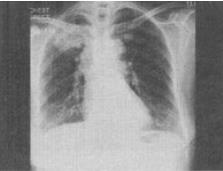

患者女,63岁,痰中带血2天,不咳嗽、发热,X线检查如图,最可能的诊断是()。

A、右上肺炎症

B、右上肺不张

C、右上肺癌

D、右上肺错构瘤

C